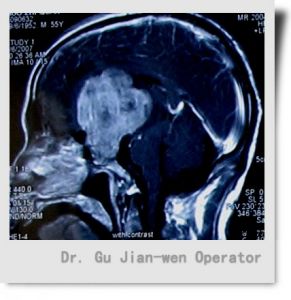

松果體區腫瘤MRI顯示圖松果體瘤導致性早熟可能由於腫瘤壓迫或破壞影響下丘腦的調節功能或HCG的分泌。神經內分泌解剖結果認為,由於腦的其他腫瘤擴大延伸到松果體引起性早熟。

松果體區腫瘤MRI顯示圖松果體的節律性活動可概括為3種:①近日節律:指MLT合成分泌呈24h周期性變化, 影響松果體MLT近日節律的主要生理因素是光照的刺激。受夜間暗光刺激信號使MLT高峰值在夜晚。②月節律:女性血中MLT波動與月經周期同步,月經來潮時,MLT升高至排卵前5倍左右,排卵前LH達高峰,MLT水平則降到最低。MLT下降對排卵可能起“允許”作用。③年度節律:生殖年度的特點是生殖力的高潮與垂體,性腺系統靜止交替出現, 這一交替現象可能由於日照期長短通過松果體影響生殖系統而實現的。

圖1 松果體區腫瘤1.腦水腫 松果體區域的腫瘤侵入第三腦室,致使阻塞,引起顱內壓升高, 常見症狀為昏睡、頭痛、嘔吐、精神異常。一般來說,阻塞越急劇,症狀發生越突然 越明顯。

松果體區腫瘤的診斷必須以病理組織學分類為依據 因為各型腫瘤的治療方案和預後差別很大,而最大的困難還是很難獲得組織學標本,因而強調立體定向松果體區病變活檢的重要性(圖1)。

2.MRI對松果體母細胞瘤診斷有獨到優點,松果體母細胞瘤起源於松果體腺, 惡性程度大,具浸潤性, 生長快,易轉移,病人存活期短, 因而早期診斷治療十分重要, MRI顯示松果體腫瘤區域的高信號以及清晰可見腫瘤侵入第三腦室的程度。